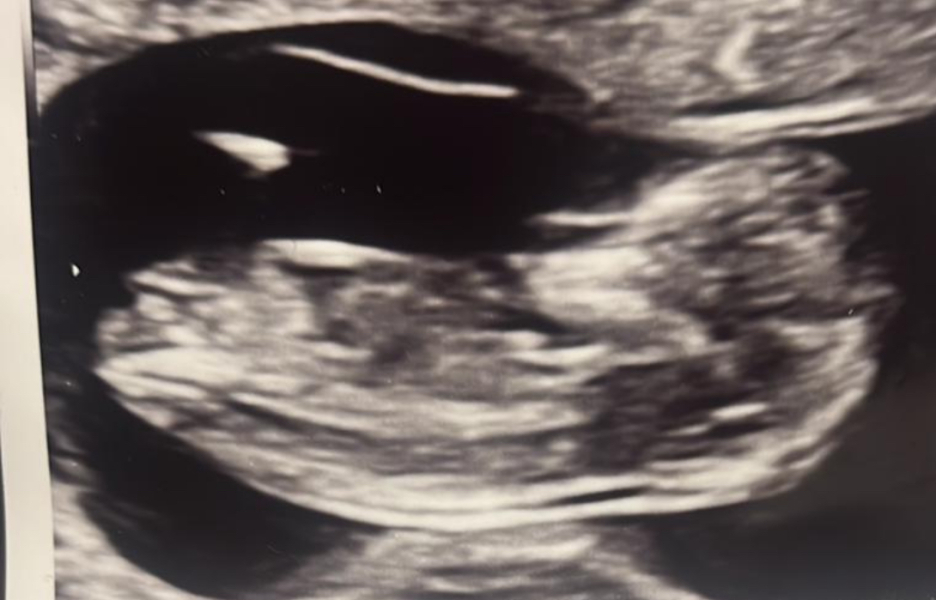

Nub theory help. Mum of 3 boys, any guesses on baby number 4?

any guesses on what baby number 4 might be?

I’m not sure there’s any nub visible so still 50/50.